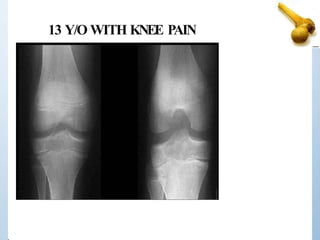

13 Y/O WITH KNEE PAIN

AGE 13

Location Epiphyseal

Margins IB

Periosteal reaction None

Matrix None

Other DX Chondroblastoma